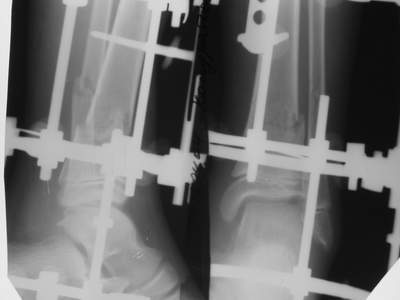

Вытяжение

|

Нашел в комп-ре схожий случай:

1) з/репозиция, 2) фиксация 2 спицами, 3) аппарат, 4) фиксационные

спицы удалены...

См. аттачт.